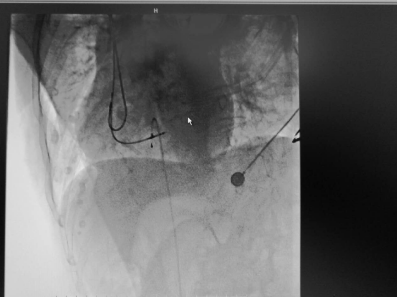

近日,在我院心血管内科病房内,70岁的患者张大爷康复出院,患者及家属握着医生的手连声道谢。谁能想到,这样一个思维清晰、开朗健谈的老人,10多天前还因为急性ST段抬高型心梗(急性心肌梗塞的一种)濒临死亡,在心脏导管室内进行争分夺秒的抢救呢! 突发胸痛3小时 70岁老人病情危急 家住江...